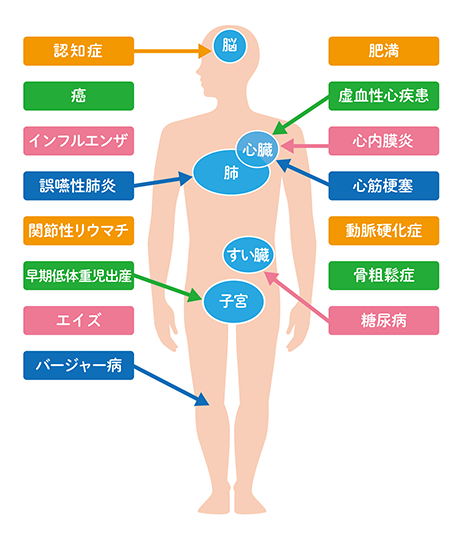

歯周病菌が作る毒素や炎症を引き起こす物質は、歯周病の病巣から血液中に入り、全身に影響を及ぼす可能性があります。

お口の中だけではなく全身の健康のためにも、歯周病は特に早期発見・早期治療を行うことが重要です。